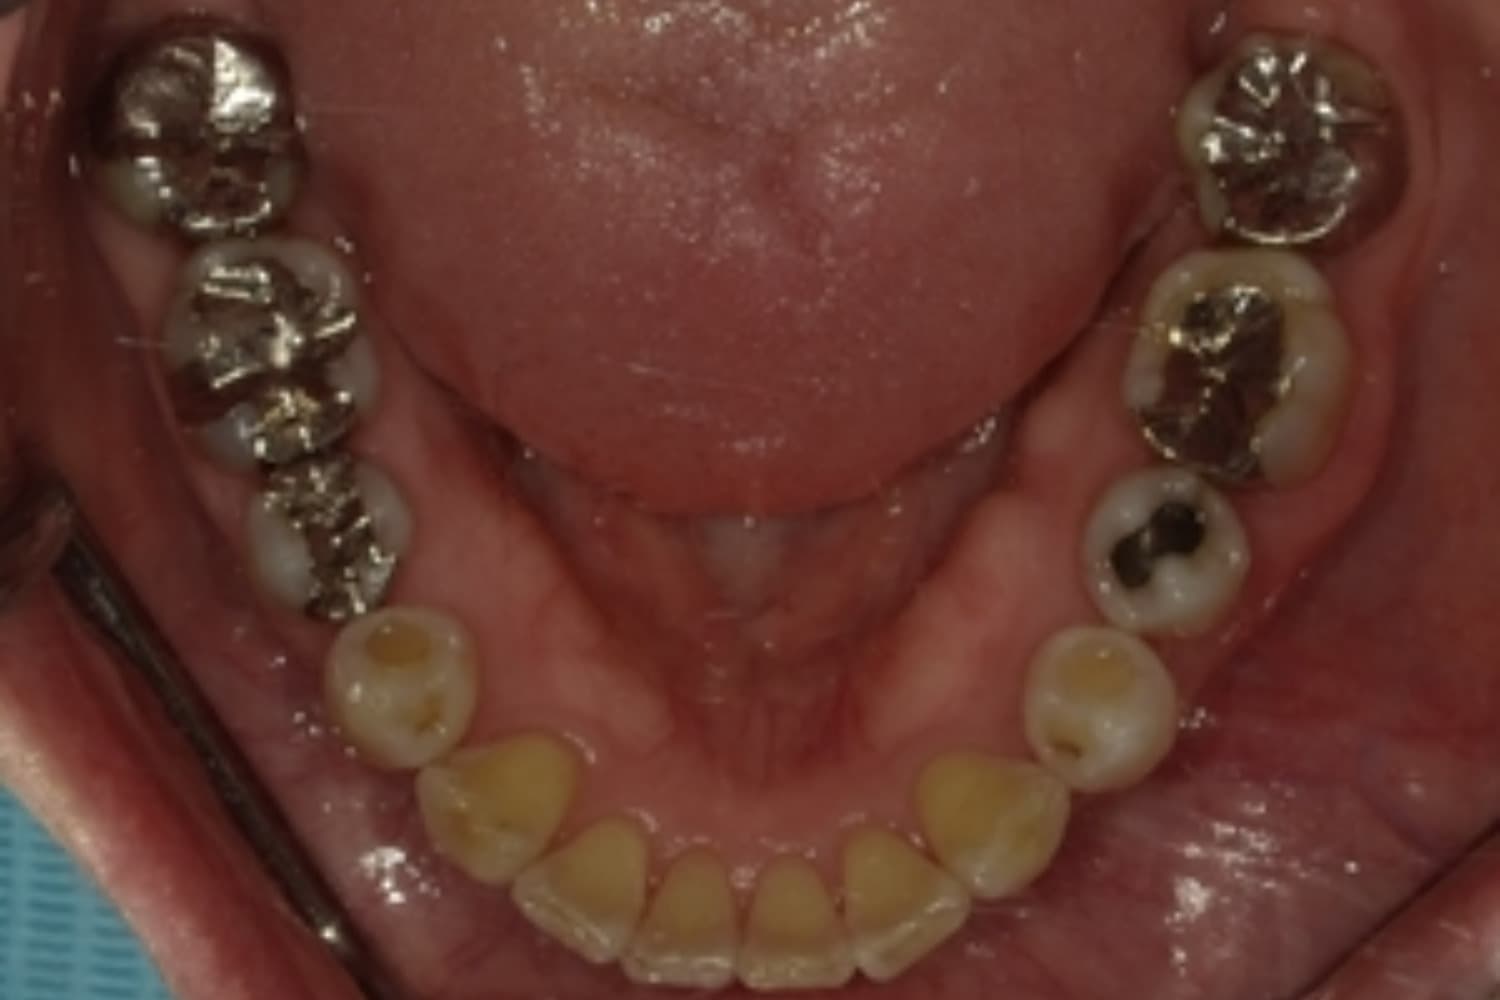

下顎大臼歯3本欠損症例

Before

After

左下第一大臼歯は保存が困難な状態であったため抜歯をおこないました。あわせて、ご来院時から欠損していた右下第一・第二大臼歯も含め、欠損部の補綴方法についてご説明し、インプラント治療を選択されました。

年齢

60歳

性別

男性

主訴

左下の第一大臼歯は別の医院で治療中でしたが、治療が思うように進まず、加えて他の箇所にも痛みが続いたことから、当院にご相談いただきました。

治療期間

10ヵ月

費用

140万円

副作用・リスク

インプラント治療は外科的な処置を伴い、多少の腫れや痛みが出ることがあります。 多くの場合は鎮痛薬で和らげることができます。